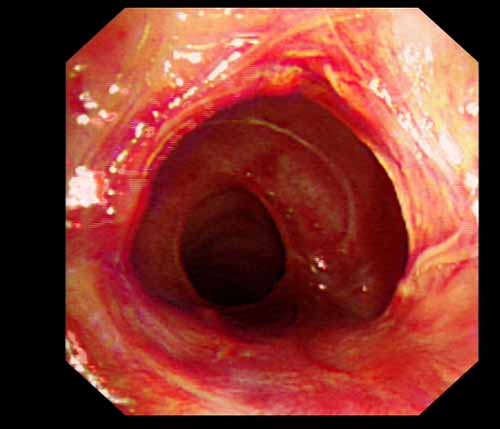

患者李某某,女,45歲,因氣管插管咳嗽、喘憋10天入院。頸部CT檢查示聲門下約20mm處氣管明顯狹窄,狹窄段長約26mm,最窄處直徑約4.4mm。支氣管鏡檢查見聲門下約2cm氣管呈漏斗狀縮窄,直徑約4-5mm,支氣管鏡無法通過。經(jīng)科室討論,決定行電子支氣管鏡下氣管球囊擴(kuò)張治療。與患者及家屬充分溝通并經(jīng)三方見證談話簽署知情同意書后,在患者持續(xù)吸氧、局麻下,科主任于世倫主任醫(yī)師帶領(lǐng)治療小組為患者實(shí)行電子支氣管鏡下氣管球囊擴(kuò)張術(shù)。手術(shù)過程順利,出血量很少,術(shù)后患者呼吸困難癥狀即可明顯緩解。10天后行二次擴(kuò)張,患者日常活動(dòng)無明顯喘憋,二次術(shù)后5天出院。

術(shù)后擴(kuò)張開的氣管管腔